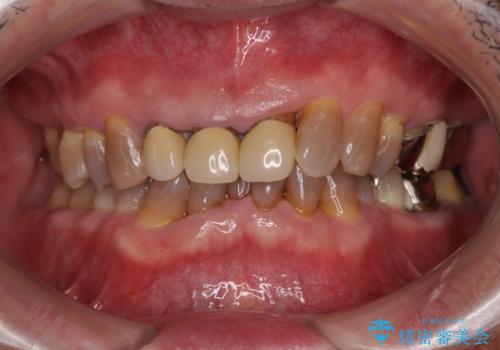

- 幼少期の薬剤の影響で歯が変色していていることを気にして来院された患者様です。

仕事も落ち着き、長年気にしていた前歯の色をきれいにしたいとのことでした。

上下ともに前歯のセラミッククラウンによる補綴治療を希望されていましたが、下顎前歯は叢生が強いため、補綴治療前に部分矯正を行って歯列を整えた上で、補綴治療を行うこととしました。